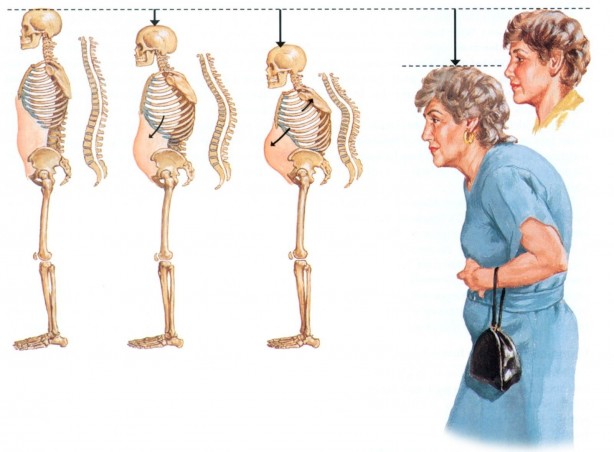

Her 3 kadının ve her 5 erkeğin 1’in görülüyor Günde sadece yarım saat ile kurtulabilirsiniz

Osteoporozu önlemenin mümkün olduğunu belirten Fizik Tedavi ve Rehabilitasyon Uzm. Dr. Öğr. Üyesi Elif Berber, “Osteoporoz önlemenin en önemli yolları D vitamini kullanmak, güneşlenmek ve kemiği güçlendirici egzersizleri uygulamaktan geçer. Yarım saatlik tempolu yürüyüşler şiddetle tavsiye edilir” dedi.